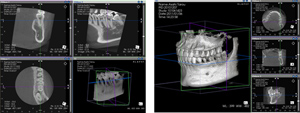

従来のレントゲン画像は平面像(二次元)でしたが、歯科用CT画像は立体画像(三次元)で表すことが可能です。例えば親知らずの歯の向きや歯根の形態、神経との距離などの三次元的位置関係を正確に診断することができます。また、インプラント治療、根管治療、歯周病治療においても非常に精度の高い診査が行えます。

インプラント治療において、埋め込みする顎の骨の状態(骨の厚み、高さ、形態、骨質など)を知ることは非常に大切です。CT画像からこれらを明確に把握することができ、神経や血管の位置も立体的に確認することができます。これにより一層正確な診断と施術ができるようになりました。

患者様に安心してインプラント治療を受けて頂くためには、顎骨の状態を三次元的に撮影できるCTレントゲンでの診断が不可欠です。